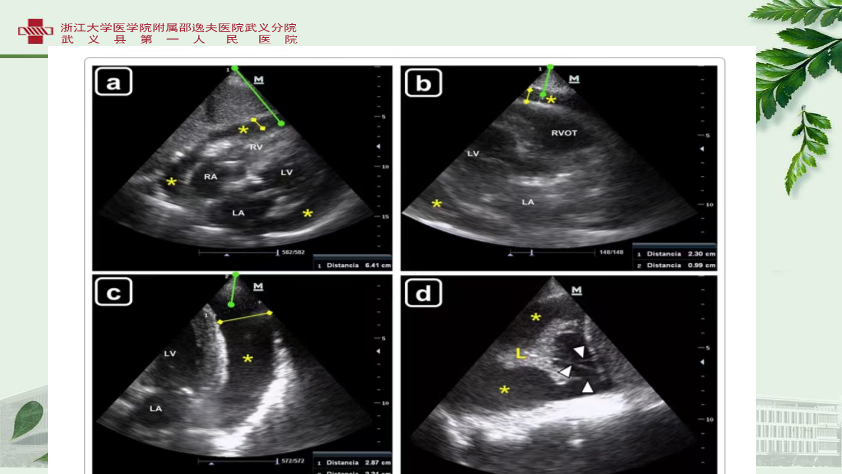

心包穿刺术